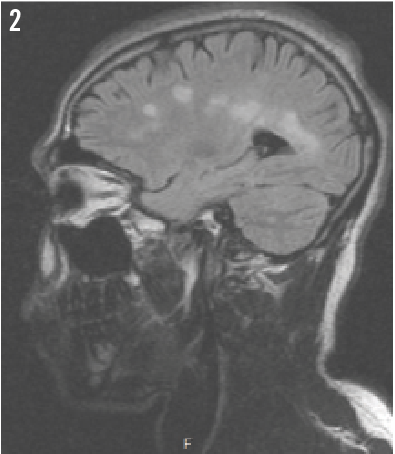

Pediatric Optic Neuritis: An Isolated Finding, or a Sign of Demyelination?

Massiel Sarmiento, MD; Sergey Prokhorov, MD; Virginia Kaldas, MD

A 17-year-old young male presented to the emergency department with sudden-onset vision loss in his right eye of 1 week’s duration...